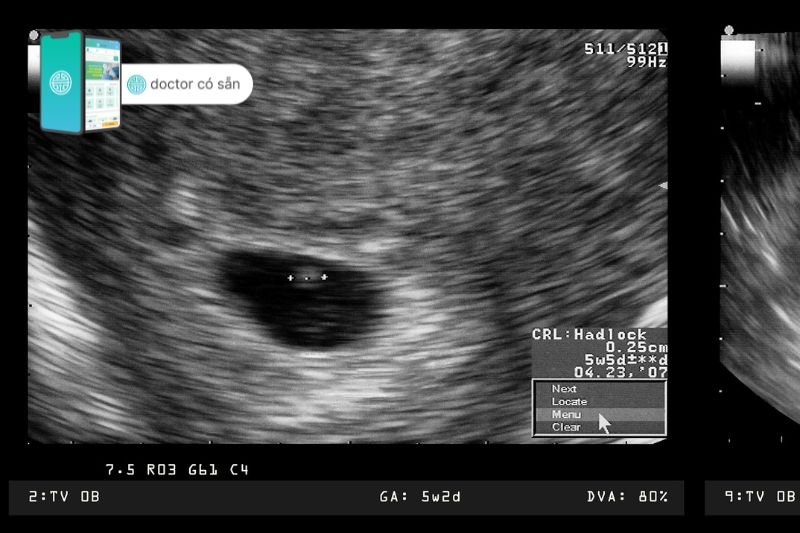

Hình ảnh quan sát được trong giấy siêu âm thai 5 tuần tuổi

Ở giai đoạn này, thứ duy nhất có thể nhìn thấy được trên giấy siêu âm thai 5 tuần tuổi là túi noãn hoàng và túi thai. Lúc này chúng ta có thể nhìn thấy một vùng tối có một vòng tròn nhỏ bên trong, phức hợp này thường được gọi là “túi phôi lòng đỏ”. Trong đó, vùng tối là túi thai và vòng tròn nhỏ màu trắng gọi là túi noãn hoàng đang bao bọc phôi có kích thước rất nhỏ bên trong.

Túi noãn hoàng có nhiệm vụ cung cấp chất dinh dưỡng cho phôi đang phát triển cho đến khi nhau thai tiếp quản sau khi mang thai. Việc nhìn thấy túi noãn hoàng có thể giúp bác sĩ khẳng định thai đã vào đúng vị trí (không phải thai ngoài tử cung).

Túi noãn hoàng được bao quanh bởi một vùng màu đen lớn hơn, được gọi là túi thai. Túi thai chứa nước ối và bao quanh phôi. Trong thai kỳ, túi thai là dấu hiệu đầu tiên có thể nhìn thấy trên siêu âm, thường vào khoảng từ 4 tuần rưỡi đến 5 tuần đầu tiên. Túi thai ban đầu có đường kính từ 2 đến 3mm, sau đó, mỗi ngày túi sẽ phát triển với tốc độ khoảng 1,1mm/ngày.

Ngoài ra, bạn cũng có thể nhìn thấy nhịp tim nhấp nháy trên giấy siêu âm thai 5 tuần tuổi. Tuy nhiên, đừng lo lắng nếu kỹ thuật viên siêu âm chưa thể nhìn thấy nhịp tim thai. Việc quan sát được tim thai khi thai bước qua tuần thứ 6 hoặc thậm chí muộn hơn sẽ phổ biến hơn.